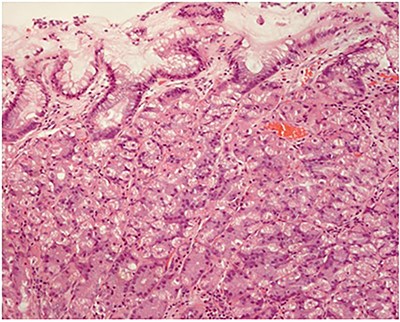

A 22-year-old male with smoking habits was periodically followed in internal medicine consultations for epigastric abdominal pain, in which, through endoscopic examinations, a Helicobacter pylori positive test was identified. Once the eradication of H. pylori was completed and confirmed, the patient started experiencing symptoms of recurrent pain in the right hypochondrium. His blood tests were normal. An abdominal ultrasound was performed, which revealed a nodular image adhering to the internal wall (not moving with positional changes) with 18 mm, found in the infundibular region. It was echogenic with an anechoic center. These aspects were compatible with sessile polyp with a necrotic center associated with surrounding parietal thickening. In order to obtain further clarification, an endoscopic ultrasonography was carried out, which confirmed a homogeneous echogenic lesion with central hypoechogenicity with a larger transversal diameter of 18 mm adhering to the wall (Fig. 1). In this context, the patient was proposed for elective laparoscopic cholecystectomy, which occurred without complications. After surgery, microscopy revealed a cavitated polyp consisting largely of gastric body mucosa, although pyloric type mucosa was still found, with no intestinal metaplasia or epithelial dysplasia being identified (Fig. 2—macroscopic examination/Fig. 3—microscopy).

Fundic (oxyntic) gastric gland mucosa (hematoxylin and eosin; ×100).